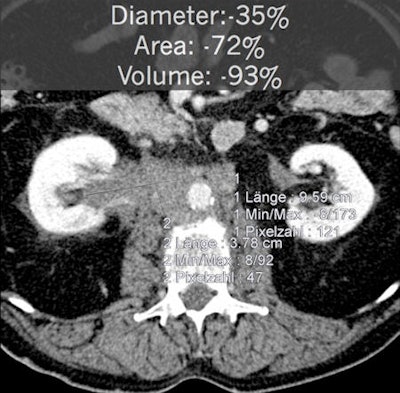

In an attempt to determine whether automated tumor volumetry was necessary or if tumor lesion volume estimates were sufficient, researchers studied 20 patients as part of the two-armed, randomized, phase II multicenter CIOX trial on metastatic colorectal cancer.

Semiautomated volumetry using a commercially available system and manual measurements of the longest RECIST 1.1 diameter and longest orthogonal diameter were performed. When comparing the manual measurements, the researchers found that simulating volume by extrapolating RECIST-based measurements would systematically overestimate tumor volume. However, volume simulations would be relatively accurate based on the World Health Organization (WHO) tumor burden criteria, Graser said.

Volumetry does offer advantages, however, Graser said.

"If you look at a new criteria like 'excellent response,' which is defined as volume reduction of more than 50%, you can now classify the patients as very good responders, as opposed to partial response, stable disease, and progressive disease," he said.